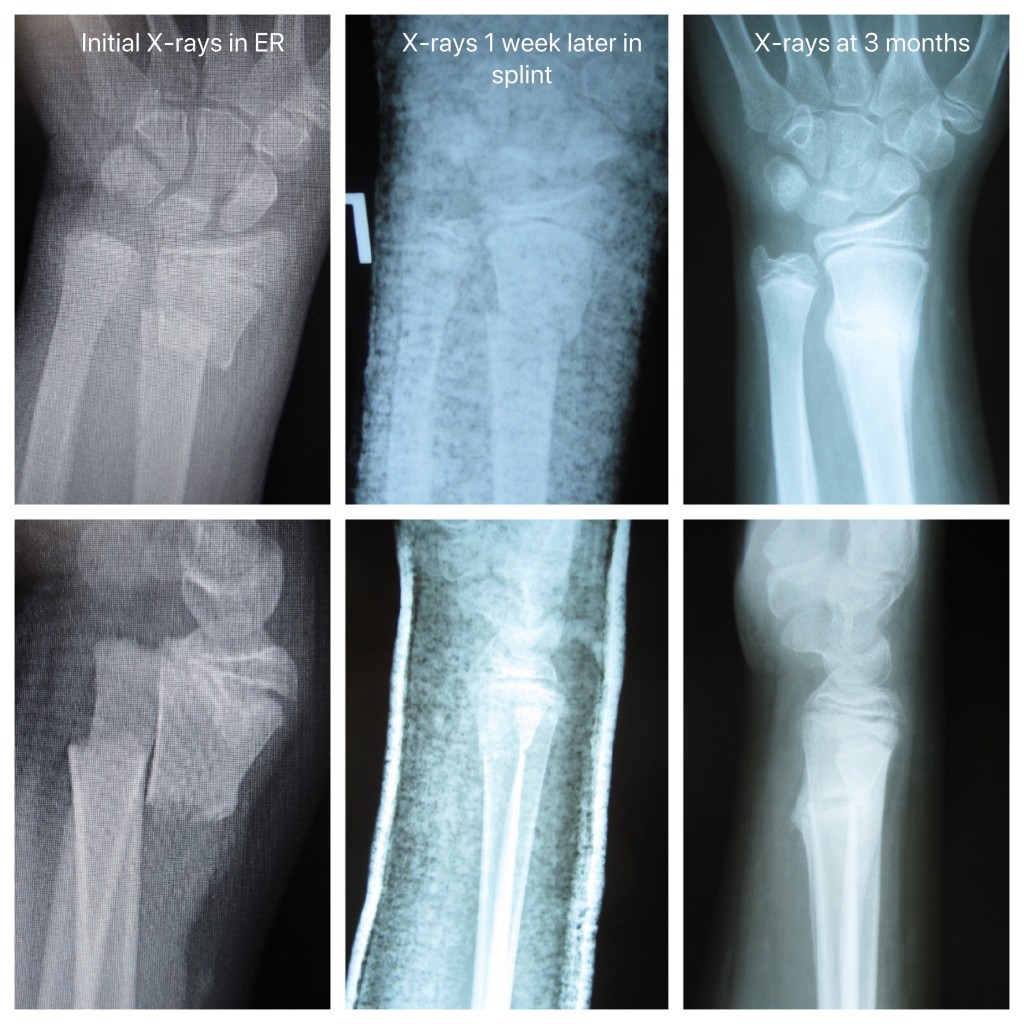

A male patient, aged 32 years old, sustained a left wrist fracture from …

Example of non-angulated wrist fracture. Initial imaging A and follow …